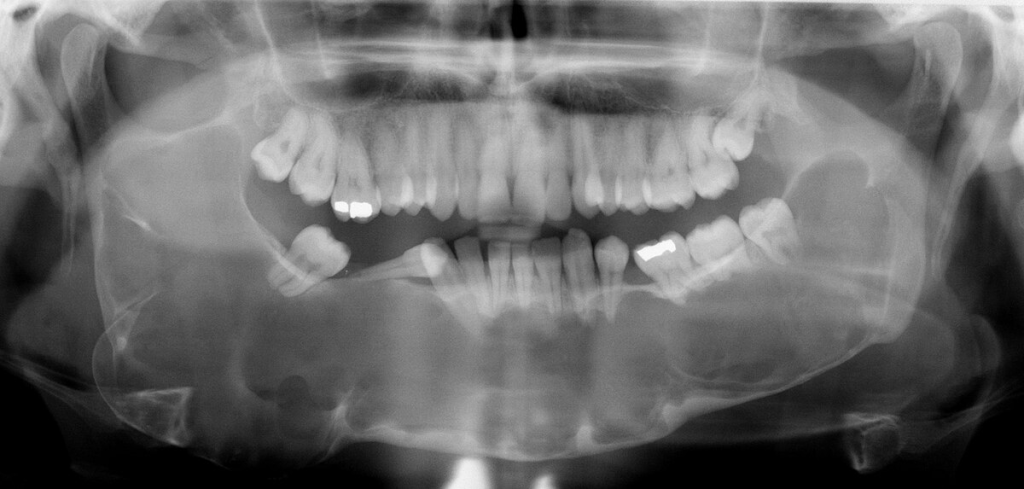

Çenelerde multipl keratokistik odontojen tümörler, yarık dudak ve yarık damak ile altçenede prognatizm saptanır.Altçenedeki kistik tümörler paresteziye neden olabilir.

Gorlin-Goltz sendromu veya Bazal hücreli nevus sendromu otozomal dominant olup ciltte görülebilen bazal hücreli karsinomalar, iskeletsel anomaliler ve çenelerde gözlenen çok sayıdaki kistle karakterizedir. Mandibular prognatizm, supraorbital sırtların belirginliği, frontal ve parietal şişkinlik, yüksek arklı damak, dudak ve damak yarığı, kaburgalarda çatallanma ile vertebra anomalileri bu sendromdaki gözlenebilen iskeletsel anomalilerdir. Odontojenik keratokistler bu sendromda karakteristiktir. Yaklaşık olarak hastaların %1i sadece çene lezyonlarına sahiptir. Lezyonlar sıklıkla mandibulada premolar-molar bölgesinde, farklı boyutlarda gözlenebilmektedir.

2-Çenenin odontojenik keratokistleri (histolojik olarak kanıtlanmış)